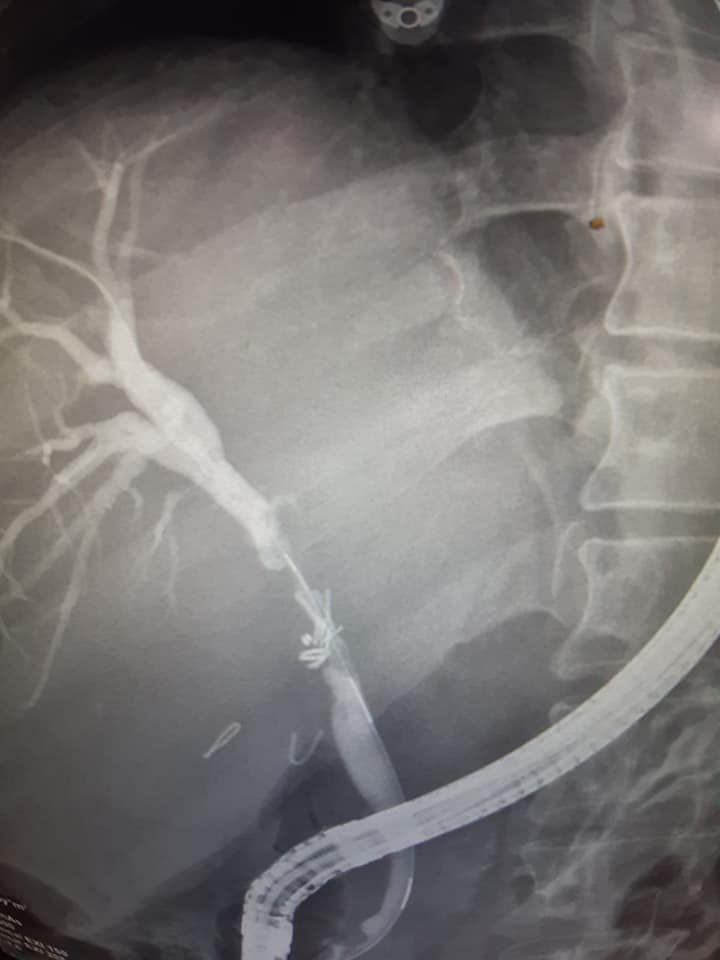

هذه الصور مع مقاطع لفيديو توضح أهمية وطريقة إستخدام مناظير القنوات المرارية لعلاج الصفراء الإنسدادية والتسريب المراري الناتج عن إصابة القناة المرارية ، وبعض هذه الحالات قد تكون حرجة وصعبة مثل هذه الحالة التي تم لها إجراء عملية إستئصال المرارة...